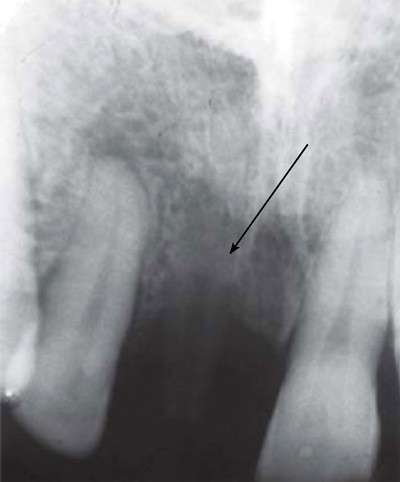

En termes de propriétés physiques, le PEEK présente de nombreux avantages. Sa densité et son module d’élasticité sont proches de ceux du tissu osseux. Il possède toutefois une limite de taille, puisqu’il est radio-transparent, ce qui complique considérablement l’analyse des clichés radiographiques pris en phase postopératoire (fig. 2) [5].